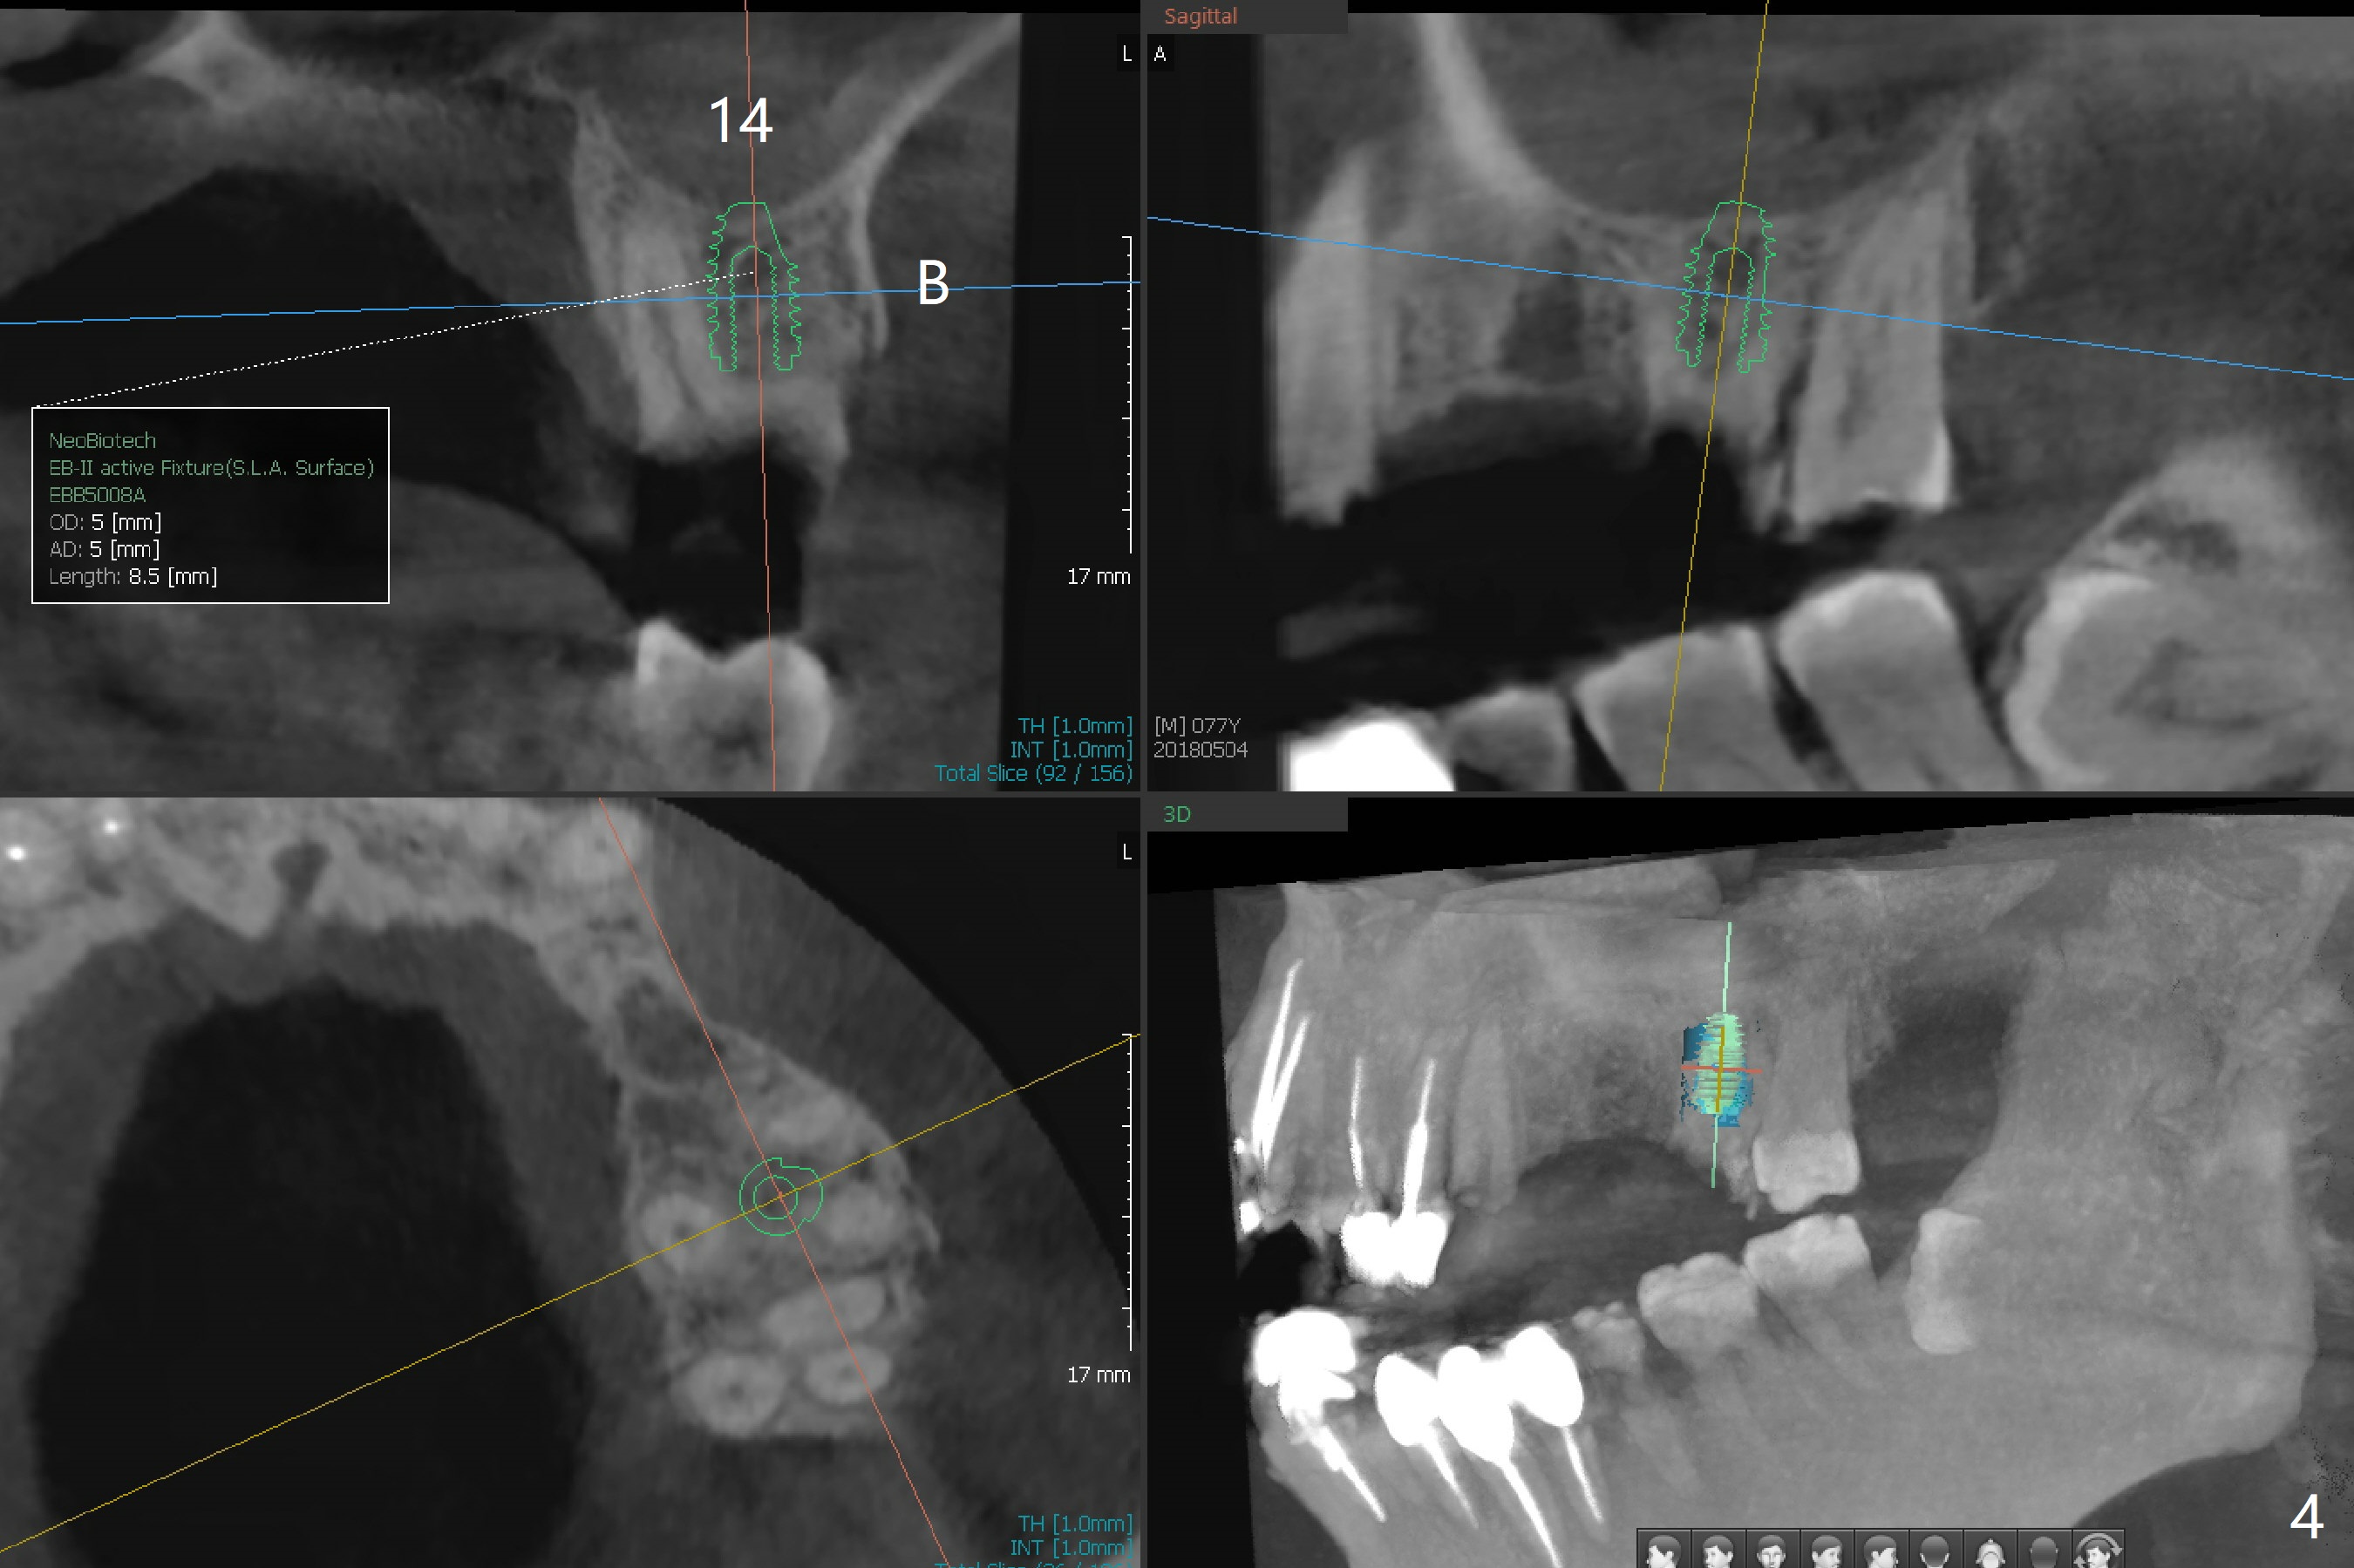

A 77-year-old man has multiple restoration with long roots (suggesting bruxism, Fig.1). The #11-14 FPD dislodges. Twenty days postop, he will travel to his home country and stays for 2 months. Four months postop, he will leave again. To strengthen provisional FPD stability and early final restoration, each implant will be placed at each edentulous area. The longest bone-level implant will be placed at #11 with bone height >20 mm (Fig.2). Since the bone width (buccopalatal) is 4 mm at #12, a 2x14(2) mm 1-piece implant is to be inserted (Fig.3); while a 3.8x10 mm 2-piece one at #13 with underprep because of low density. As the septal bone height is limited at #14 (Fig.4), a 5x8.5 mm implant is going to be placed.